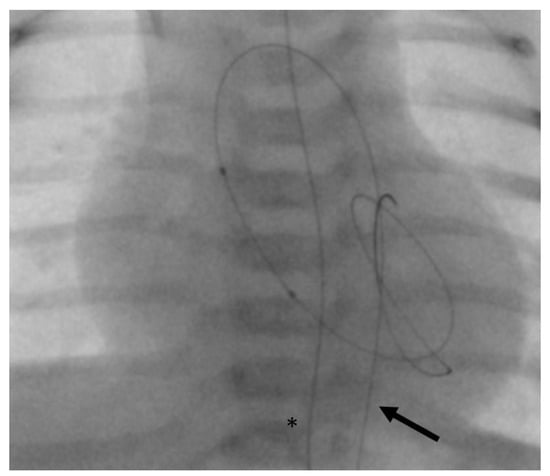

- In the same patient, an aortic wall injury resulting in a constriction of the intima following the second BAV occurred (Figure 9). However, this constriction was without significant stenosis and was corrected at the time of necessary aortic valve repair.